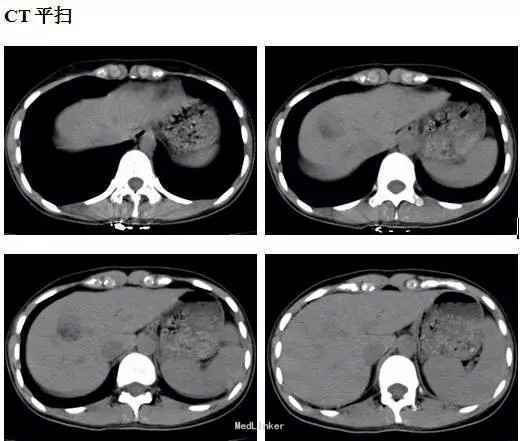

患者,女,26岁,因体检发现右肝占位8天入院,超声提示血管瘤。无不适主诉,既往体健。

体检:腹平软,无肠型及蠕动波,未见腹壁静脉曲张,肝脾肋下未及,肝区无叩击痛,全腹无压痛、反跳痛、肌紧张。腹水征阴性。 CT表现:肝右前叶可见类圆形等低混杂密度影,边界尚清,直径约2.5cm,CT值-20~35HU,;增强后动脉期病灶呈结节样强化,门脉期病灶包膜强化更明显,有逐渐向中心填充趋势。